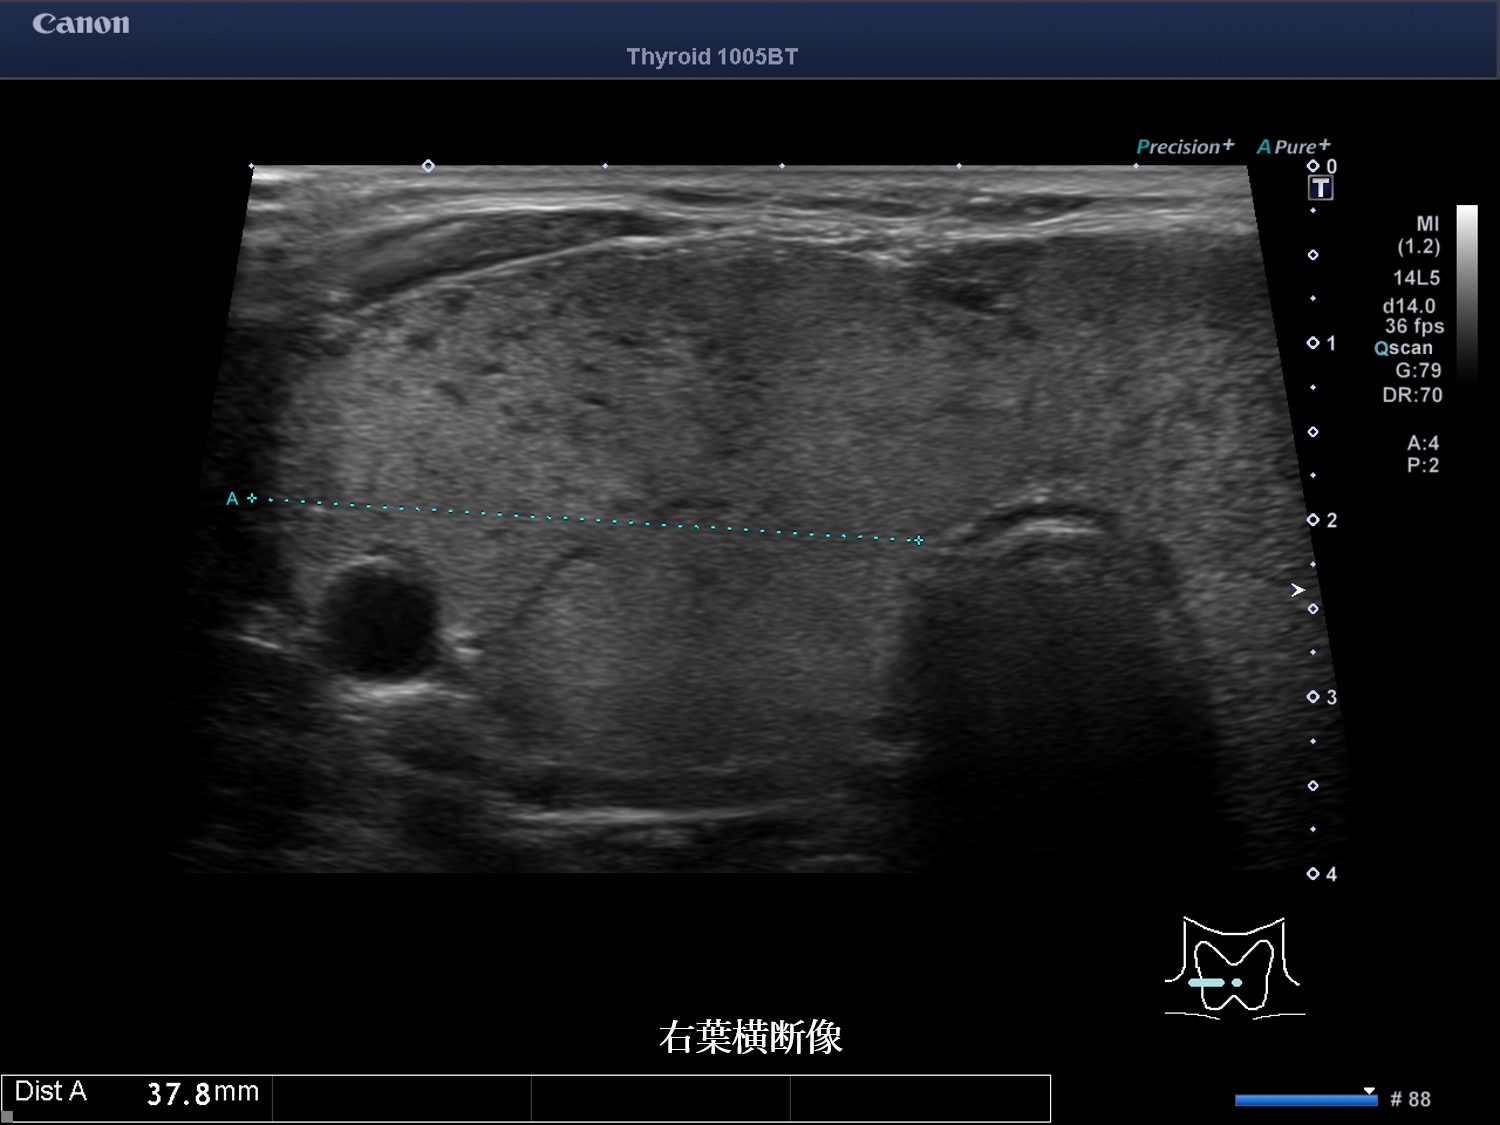

甲状腺超音波 動画 右葉横断像 カラー(No20-21_A)

甲状腺超音波画像 画像1(No20-21_1)画像2(No20-21_2)画像3(No20-21_3)

誤っている超音波所見はどれか。

① 結節性病変は認めない

② びまん性に腫大している

③ 内部エコーは不均質である

④ 甲状腺内血流は増加している

⑤ 低エコー域内の血流低下を認める